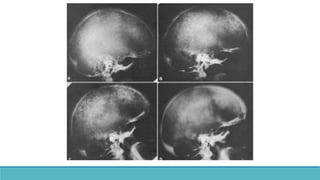

Single-isotope dual-phase (early- and delayed-phase) scintigraphic technique :

• 99mTc sestamibi consists of lipophilic cationic molecules.

•After intravenous injection, the molecules are distributed according to blood flow in the body, cross the

cell membranes by passive diffusion, and become concentrated intracellularly in the region of the

mitochondria

•99mTc sestamibi washes out more rapidly from the thyroid gland than from hyperfunctioning parathyroid

glands.

•It is normally is distributed to the parotid and submandibular salivary glands, thyroid gland, heart, and

liver, mild generalized uptake in the bone marrow.

•In younger individuals, mild to moderate thymic uptake and brown fat uptake may also be seen.

• Uptake is not seen in normal parathyroid glands.

• Single injection of 99mTc sestamibi, followed by imaging at approximately 10–15 minutes and 1.5–3

hours after the injection.

• Parathyroid adenoma showing delayed washout.

SPECT